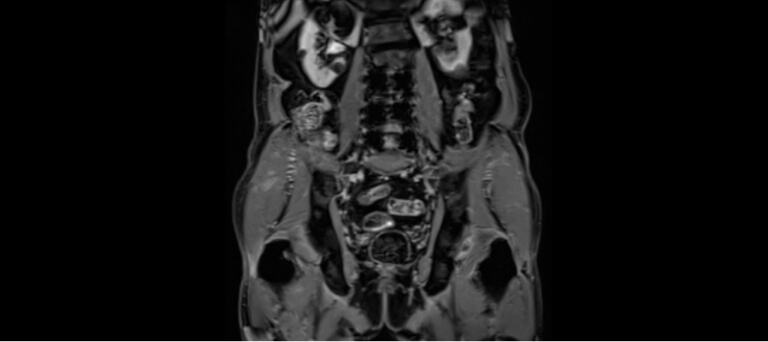

Resonancia Magnética Multiparamétrica de Próstata:

La resonancia magnética multiparamétrica (mpMRI) es una técnica de imagen avanzada, no invasiva, que permite visualizar la próstata con gran detalle y precisión.

Actualmente recomendada por guías internacionales en Estados Unidos y Reino Unido, esta prueba ayuda a identificar la presencia de lesiones con características sospechosas de cáncer, sin necesidad de procedimientos invasivos.

En nuestra Unidad Urológica contamos con esta tecnología, disponible en pocos centros en México, lo que nos permite ofrecer diagnósticos más precisos y personalizados para cada paciente.